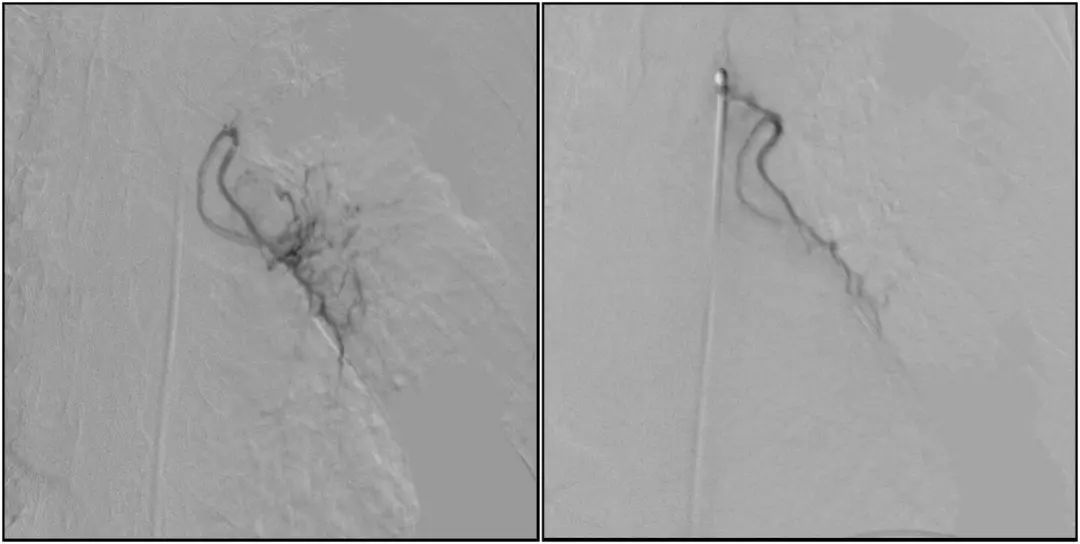

支氣管動脈栓塞+化療灌注術

在普愛醫療移動式平板介入中C影像的引導下,醫生為患者實施雙側支氣管動脈栓塞+化療灌注術。

在微導絲的配合下,先后分別超選擇①至3支左側支氣管動脈腫瘤供血動脈,經微導管推注栓塞微粒球栓塞腫瘤動脈。栓塞結束后,再次用移動式平板介入中C做造影檢查,見腫瘤染色消失。

術前術后對比影像